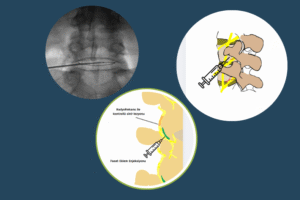

Faset eklemler omurganın arkasındaki küçük eklemlerdir. Bu eklemlerde gelişen ödem ve iltihap ağrıya yol açabilir. Steroid enjeksiyonu ile bu bölgeye müdahale edilerek ağrı azaltılır.

Bu işlemde, ağrı iletimini sağlayan sinir uçlarına özel bir radyofrekans enerjisi uygulanarak kontrollü bir lezyon oluşturulur. Böylece hasta ağrıyı hissetmez hale gelir. Etkisi genellikle 6 ay ile 1 yıl arasında sürebilir.

Sinir kökü çevresindeki ödem ve iltihabı azaltmak için uygulanan bir yöntemdir. Bu işlemle hem bel ağrısı hem de bacağa yayılan ağrı kontrol altına alınabilir.

Ameliyat sonrası bel ağrısı, çoğu zaman geçici bir süreçtir ve uygun fizik tedavi ile kontrol altına alınabilir. Ancak bazı durumlarda bu ağrılar faset eklemlerden veya sinir köklerinden kaynaklanabilir. Bu gibi durumlarda, faset blokajı, termokoagülasyon veya epidural enjeksiyon gibi yöntemler oldukça etkili ve güvenli seçeneklerdir.